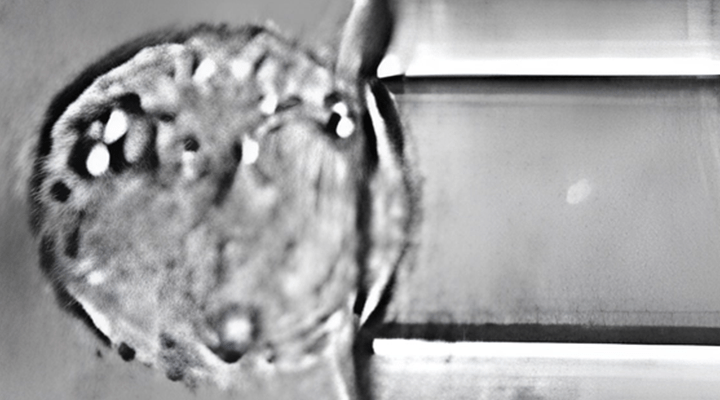

The compact device fits on any laboratory bench or under a clean-bench hood. The physical force sensor is an ultra-thin, flexible, and biocompatible PDMS membrane forming the bottom of a cell culture cylinder on which cells are seeded: The CellDrumTM. In addition to biological applications, CFArefer

The device uses quality-tested CellDrum sensors to detect minute contractions of the silicone membrane caused by cellular forces. These are then measured and analyzed.